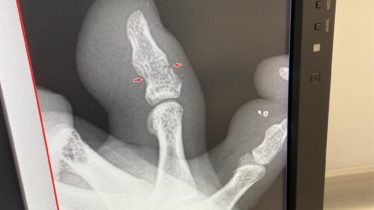

【痛いヤツ】32歳美容師、やってしまいました。

休みの朝にやってしまいました。なんって日だ!!人生初体験。まさかこの年齢でこんな事でやってしまうとは。骨折!!マジびっくりもんです。折れると思わんかった。まさかと思いますが、本棚に足の指をぶつけただけでwww今は笑えますがぶつけた時は洒落に...